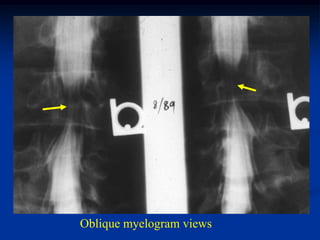

Case #1102

Axial and coronal CT scan

37 year male with chordoma in body of L-4

CT scan myelogram with block at L-4

Myelogram showing block

at the L-4 level

Oblique myelogram views